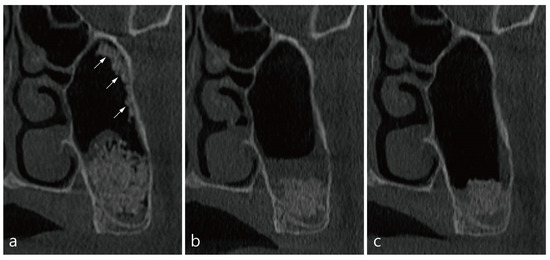

6. Case 4